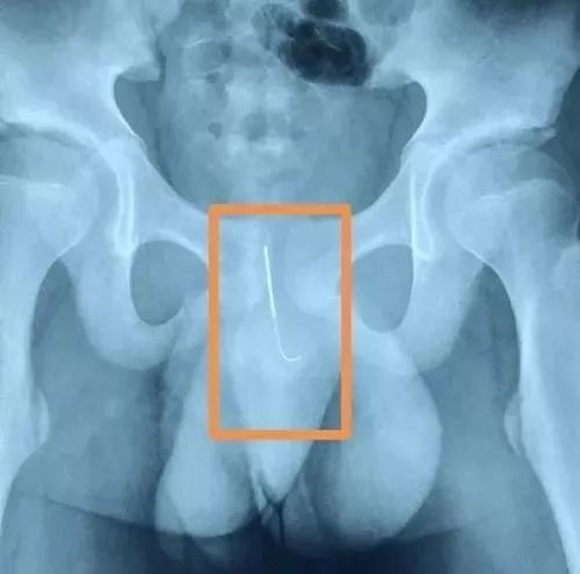

Trang Sohu đưa tin, bé trai tên Tiểu Long, 12 tuổi sống ở Thiểm Tây, Tây An, Trung Quốc vừa trải qua một cuộc phẫu thuật để rút một cây kim 11cm ra khỏi dương vật. Theo đó, câu chuyện đằng sau sự cố này khiến nhiều người không khỏi giật mình.

Vào 3 giờ sáng ngày 26/7, bệnh viện Nhi Đồng Tây An tiếp nhận trường hợp này. Phó giám đốc khoa tiết niệu bệnh viện Nhi đồng Tây An - Vương Thịnh Hưng cho biết, khi nhập viện Tiểu Long bị đau nhiều tại bộ phận sinh dục. "Cậu bé gặp khó khăn trong việc đi tiểu vì kim châm cứu đã đâm vào niệu đạo và gần đến bàng quang, vô cùng nguy hiểm. Vì kim rất mỏng và dài nên có khả năng khiến những bộ phận khác gặp nguy hiểm, nên cần phải phẫu thuật càng sớm càng tốt để lấy kim ra", bác sĩ Vương nói.

Cây kim dài 11cm được Tiểu Long đưa vào dương vật để giúp tỉnh ngủ khi làm bài tập về nhà.